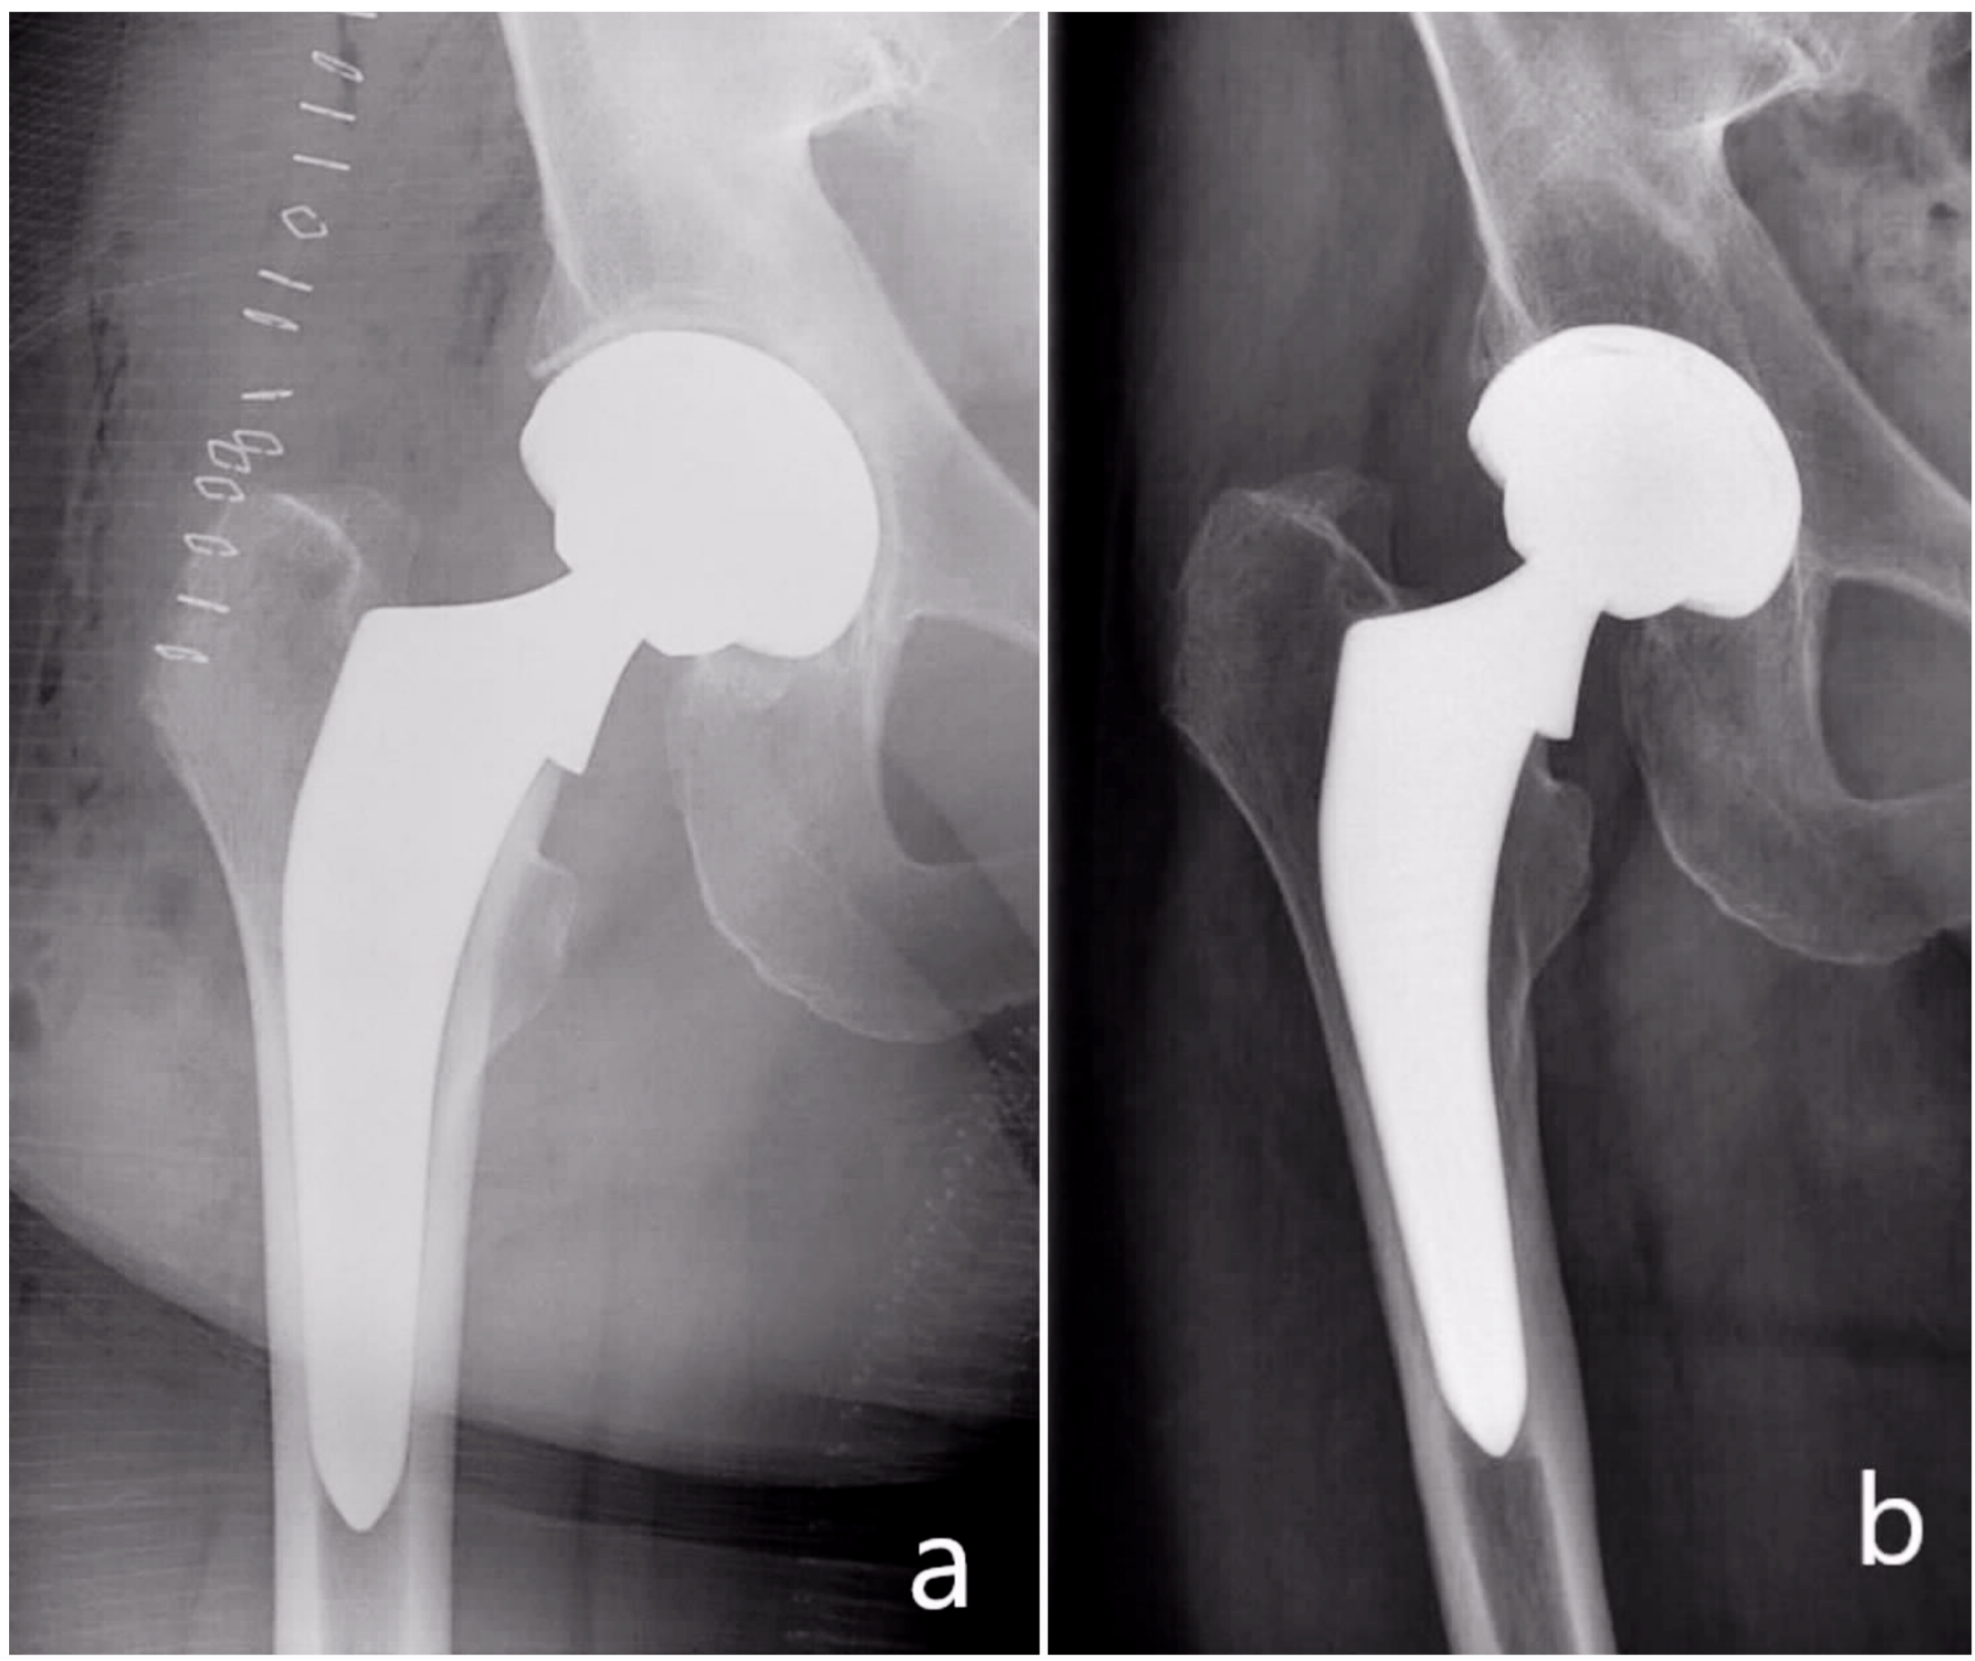

5-Year Clinical and Radiographic Results of the Direct Anterior Approach for Total Hip Arthroplasty Using a Collared Cementless Femoral Short-Stem Prosthesis

Clinical and Radiological Outcome

4.2. Radiological Outcome